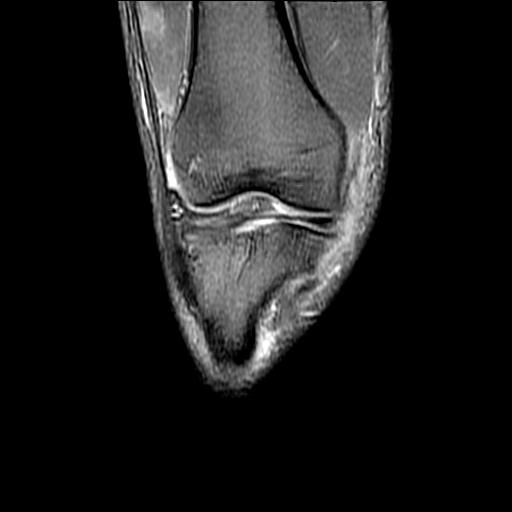

标题: MRI1265:男性40岁,右膝关节 [打印本页]

标题: MRI1265:男性40岁,右膝关节

40岁男性,右膝关节外伤,x光平片示,髁间隆突撕脱骨折。

1、前交叉韧带撕裂;

2、外侧半月板后角撕裂;

3、关节腔积液。

前交叉韧带撕裂,关节腔积液.

半月板1-2级损伤   前交叉韧带撕裂伤   关节腔少量积液  诸骨未见新鲜外伤性改变

髁间隆突撕脱骨折;内侧副韧带损伤。

1、内侧副韧带撕裂;

2、前交叉韧带撕裂;

3、滑膜炎伴关节腔积液。

内侧副韧带撕裂及关节腔积液是肯定的,但是前交叉撕裂确定吗?会不会有容积效应的因素,因为前一张前交叉显示清楚,连续性良好,且较光滑。请问楼主有关节镜支持吗?我们医院也经常有这样的患者,但苦于没有关节镜,而无法对照、证实(除非完全断裂),出现了不同的诊断结果只能毫无意义的争论。

1、前交叉韧、内侧副韧带撕裂;

3、关节腔积液。4、髁间脊撕脱骨折。